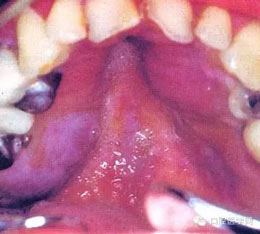

(六) Kaposi肉瘤: 主要發(fā)生于軟、硬腭粘膜。